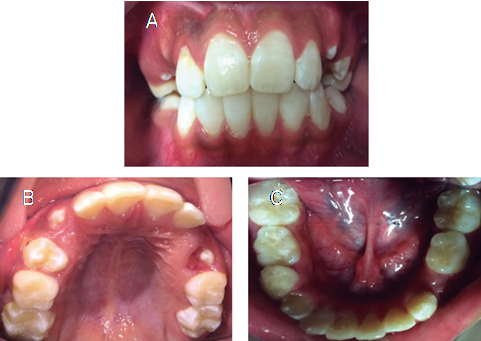

Intraoral examination. The patient´s oral cavity exhibited an almost completely erupted mixed dentition, good-shaped dental arches with a very mild incisor crowding, excessive plaque accumulation, and halitosis, indicating neglected oral health and hygiene procedures. The incisor labial faces exhibited white/yellow spots, likely due to enamel fluorosis (Figure 1). Shallow carious cavities were present in the first four permanent molars. The patient exhibited a mild fissured geographic tongue; however, gingiva, other soft tissues, and tonsils did not exhibit any abnormalities.

Dental treatment. Based on the child’s oral and medical care needs, it was decided to manage the patient in an interdisciplinary manner, including the dental team, the psychiatric, and a pediatric nurse. The girl’s caretaker agreed the proposed dental treatment plan through the signature of an informed consent form. Then, with the psychiatrist's approval and guidance, an in- depth oral prophylaxis was carried out during the initial three appointments, in which the patient was continuously psychologically approached by the pediatric dental staff and the nurse. The restorative procedures included several resin restorations and pit-fissure sealants, under local anesthesia and rubber-dam isolation, on the first four permanent molars. Fluoride varnishes were also applied. The entire treatment was completed in six weeks (Figure 2). Regarding the girl’s behavior on the dental chair, she became fairly cooperative with some crying episodes and occasional arm movements towards her mouth, interrupting briefly the implementation of dental procedures. Once the restorative treatment finished, the patient and her caretaker were provided with detailed educational and motivational long-term strategies for improving her oral hygiene at home on a daily basis; they also received nutritional advice. For control reviews and the reinforcement of preventive habits, future appointments were carefully scheduled. No additional oral anomalies were found in the last visit.